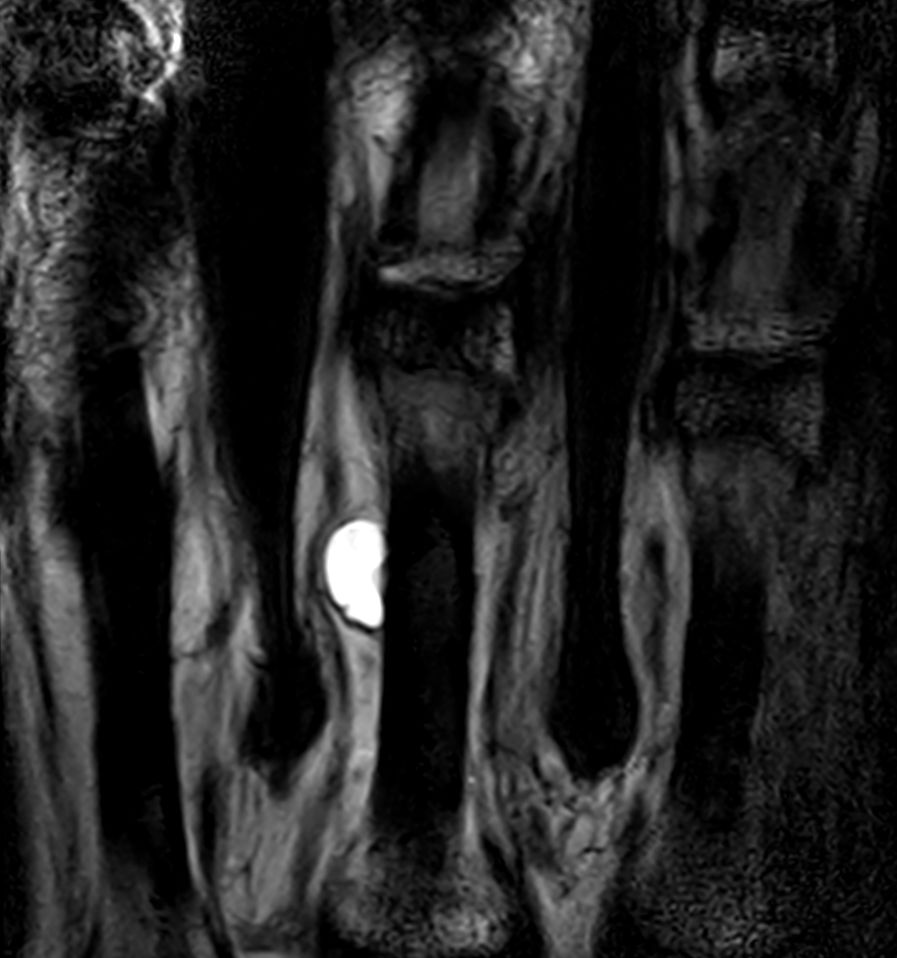

Patient with a ganglion in his finger. dS Microscopy coil set is used, consisting of two 47 mm coils, for small field-of-view imaging with high in-slice spatial resolution and a high signal-to-noise ratio. Compressed SENSE is used in all sequences to shorten the overall exam time for the patient.

Coronal T2w TSE Compressed SENSE